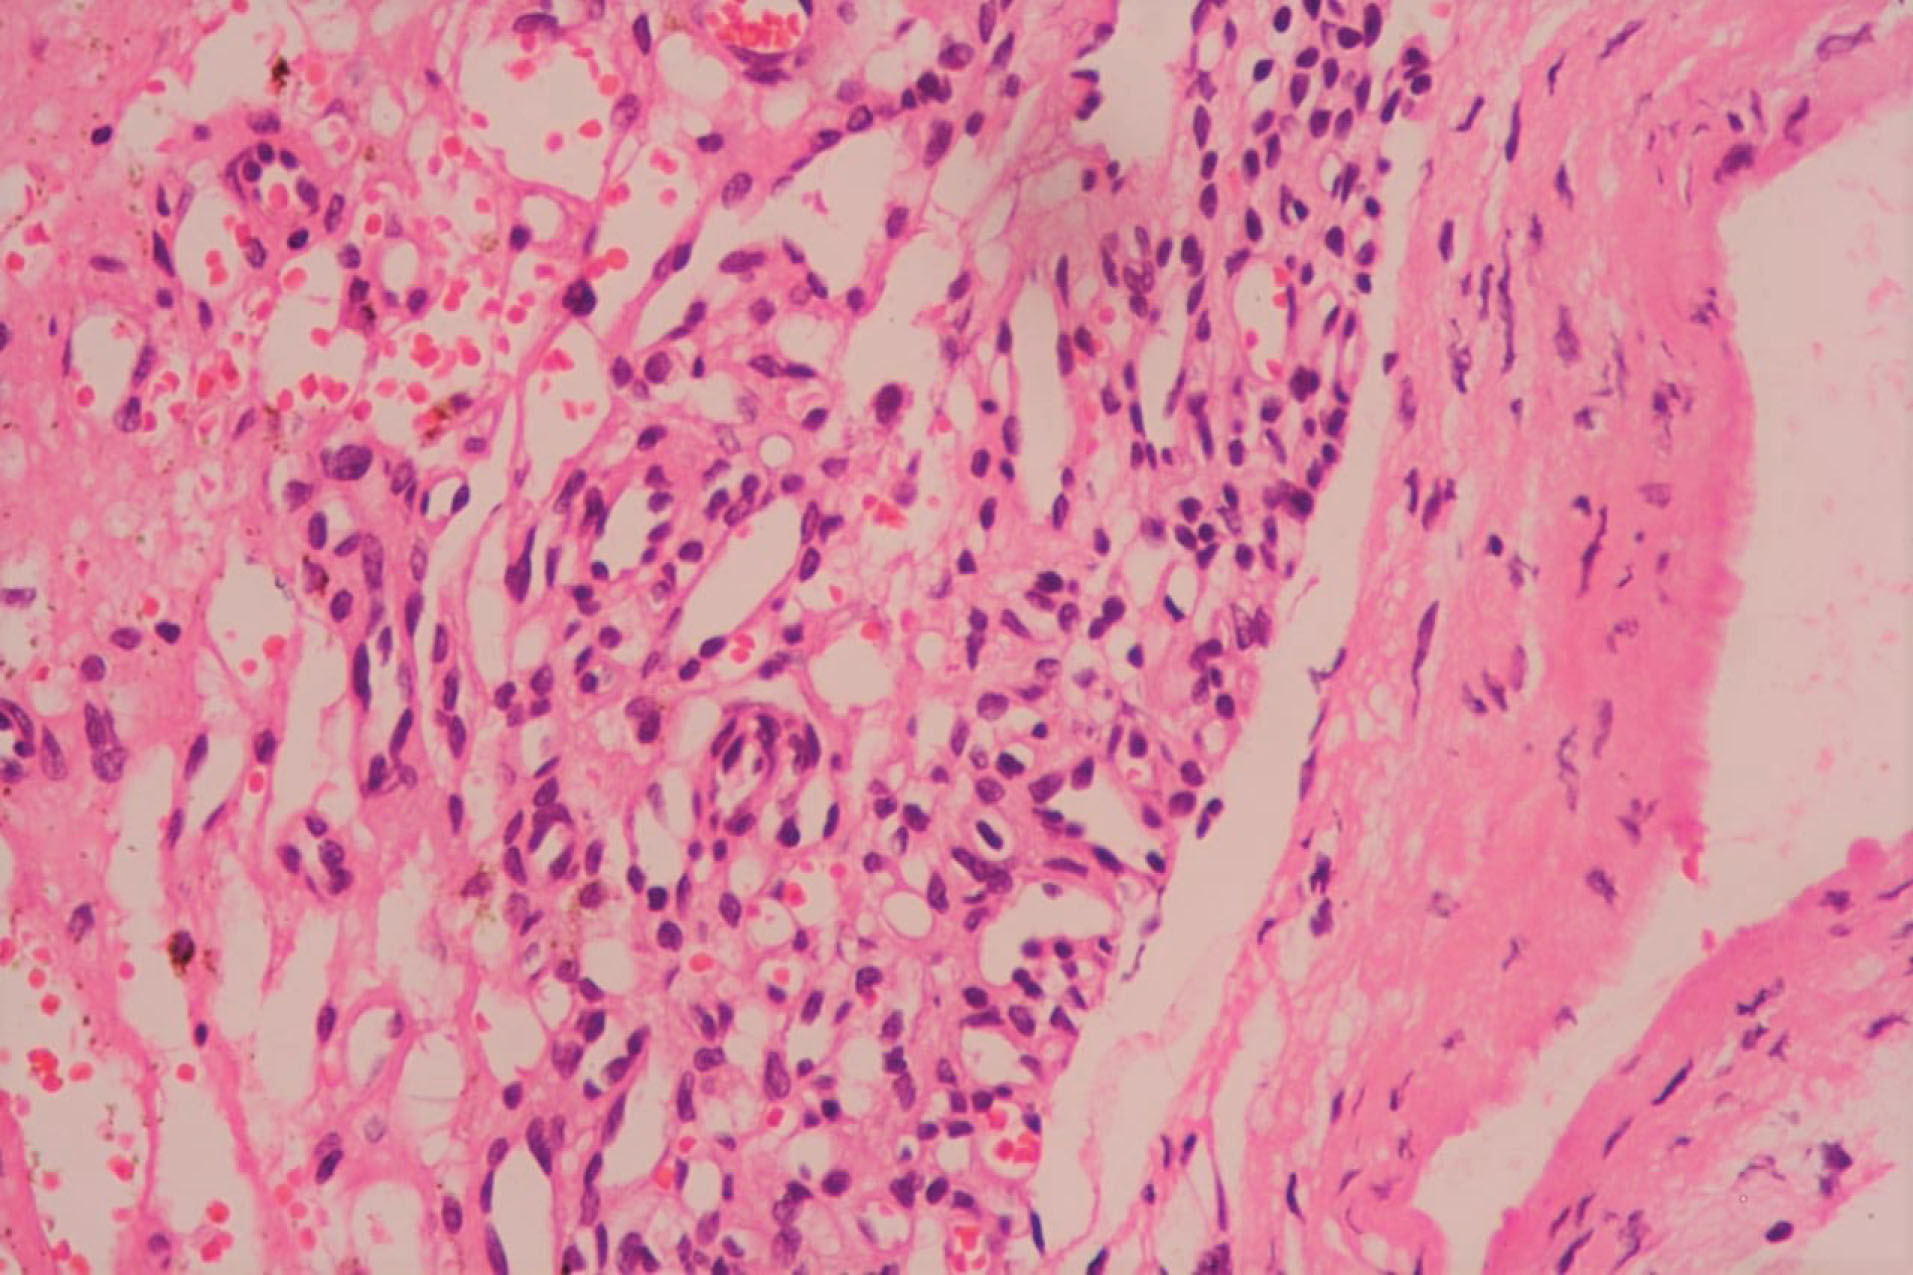

The patient underwent midline sternotomy under general anaesthesia for planned pericardial window surgery with diagnostic and therapeutic intent for the mass after thorough preoperative workup including ultrasonography of Abdomen and pelvis region. After opening pericardium, we found encapsulated, firm, highly vascular mass immediately adjacent to the main pulmonary artery and extending towards the posterior wall of right ventricle. Since the mass seems to be part of the right ventricular wall, resectability was deemed as difficult. Hence, only careful partial mass resection without any cardiac reconstruction was done after taking pledgeted polyprolene sutures around planned excision areas, to prevent torrential bleeding or cardiac rupture. Overlying total pericardium was removed to make left sided pleuropericardial window. Procedure went smoothly and post operatively patient did well. The histopathology examination revealed multiple vascular like structures and small capillary type vessels suggestive of a capillary type haemangioma without mitosis ( and ). She is currently asymptomatic with no recurrence of any pericardial or pleural effusion after regular follow-up of six months.

jcvtr-13-250-g004

Figure 4. High power microscopic view showing tumour composed of tiny capillary sized vascular spaces which are lined by plump endothelial cells. Scant fibrous stroma with foci of haemorrhage are also seen. (x400, Hematoxylin & Eosin).